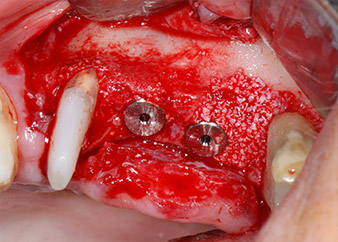

Les implants (Restore, Keystone Dental, 3,75 mm de diamètre, 8,0 mm de long) ont été mis en place à l'aide du moteur d'implantologie (Fig. 11 et 12).

Les défauts osseux autour des implants, sur la face mésiale de la dent 27 et autour de la racine de la dent 24, ont été reconstruits par des particules de substitut osseux xénogénique et recouverts d'une membrane collagène résorbable (Bio-Gide, Geistlich Biomaterials) pour une augmentation par GBR (Fig. 13 et 14).